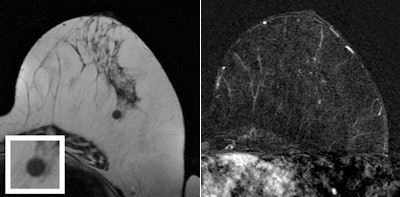

B-mode ultrasound scan shows hypoechoic mass with ill-defined margins in left breast at 1 o'clock position. T2-weighted turbo spin-echo MR image and magnification view (left) show a round mass as the correlate of the mammographic finding at 1 o'clock in the left breast. The mass is isointense with discrete internal septations. Subtracted T1-weighted gradient-echo MR image (right) obtained after administration of contrast shows no enhancement of the lesion. Ultrasound-guided core needle biopsy was performed, and histologic examination showed a sclerosed fibroadenoma.

T2-weighted turbo spin-echo MR image and magnification view (left) show a round mass as the correlate of the mammographic finding at 1 o'clock in the left breast. The mass is isointense with discrete internal septations. Subtracted T1-weighted gradient-echo MR image (right) obtained after administration of contrast shows no enhancement of the lesion. Ultrasound-guided core needle biopsy was performed, and histologic examination showed a sclerosed fibroadenoma.Proceed with caution?